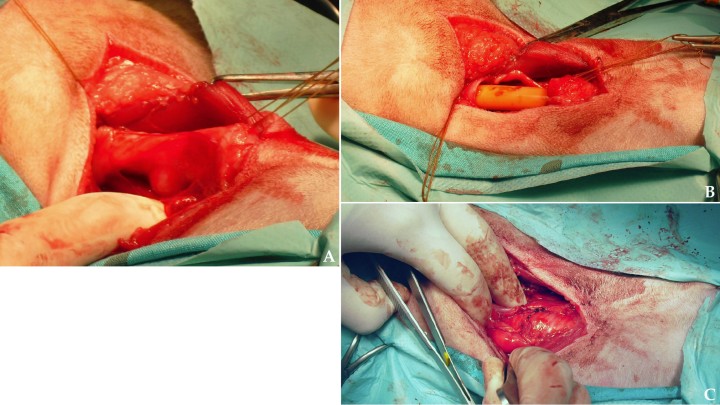

El tratamiento realizado fue la resección quirúrgica mediante una traquectomía parcial. La incisión abarcó un par de anillos traqueales tanto craneal como caudalmente al nódulo traqueal (Fig. 7) y la sección de tráquea resecada fue remitida para su estudio histopatológico, el cual confirmó el diagnóstico de linfoma traqueal de bajo grado y ausencia de células tumorales en los bordes del segmento traqueal seccionado.

<p>Imágenes intraoperatorias de la traquectomía. (<strong>A</strong>) Se visualiza que, tras la disección del área afectada, el nódulo traqueal hace prominencia también hacia el exterior de la pared traqueal. (<strong>B</strong>) Imagen tras la resección de la zona tumoral tomando dos anillos traqueales sanos a ambos lados. (<strong>C</strong>) Anastomosis termino-terminal con puntos sueltos con material monofilamento reabsorbible.</p>

Imágenes intraoperatorias de la traquectomía. (A) Se visualiza que, tras la disección del área afectada, el nódulo traqueal hace prominencia también hacia el exterior de la pared traqueal. (B) Imagen tras la resección de la zona tumoral tomando dos anillos traqueales sanos a ambos lados. (C) Anastomosis termino-terminal con puntos sueltos con material monofilamento reabsorbible.